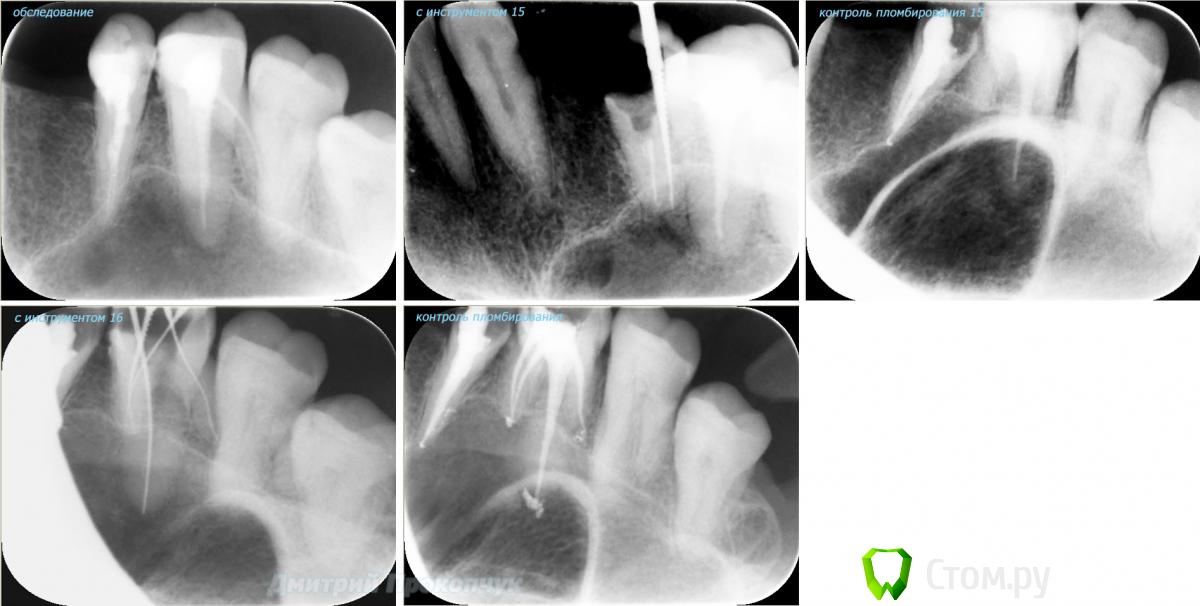

punkrat Опубликовано 16 сентября, 2014 Поделиться Опубликовано 16 сентября, 2014 Коллеги, тема , возможно, не имеет смысла просто приятная мне эндодонтия, сохранил с предыдущего места работы. Да, будь я проклят, я все знаю, НИГДЕ НЕТ КОФЕРА, на новом месте с этим норм. В общем если посчитаете, что я недостоин постить тут свои снимки, то так тому и быть, удалю тему.. 01. плановый ретрит 46ого и результат через 7 месяцев. Осложняющим моментом тут было то, что длина каналов была около 26 мм... 02. первичное эндо 34 (подготовка к ортопедии) + бонус - ретрит 35 03. ретрит 26 (подготовка к ортопедии) 04. ретрит 15, 16 (подготовка к ортопедии). основная сложность была в ретрите 15 - он был запломбирован термафилами, да еще снабжен свш... 05. ретрит 27 (подготовка к ортопедии). Ничего особенного, со временем посмотрим какова будет убыль этого совсем немаленького разрежения 06. ретрит 13. Разумеется пришлось выбивать вкладку, а потом еще попилить 3-4 миллиметра цемента, но, таки попилил куда нужно... 07. ретрит 17 (подготовка к ортопедии). В данном случае я, кажется, потратил больше времени на снятие литого моста, чем на лечение 17)) 08. ретрит 16 (подготовка к ортопедии). Снимка с инструментом нету, поскольку, визиограф сломался и его делал на пленку. 15 разумеется тоже перелечен... 09. плановый ретрит 16 10. первичное эндо 36, рядовой случай что дистальный щечный удалось найти не сразу, он был спрятан под нависающим дентиклем 11. ретрит 12, 11 (подготовка к ортопедии). Казалось бы, рядовой случай, если бы корневые каналы обоих зубов не были бы налухо забиты резорцин-формалиновой смесью... 12. ребенок 9ти лет, острый пульпит 46, попробовал оставить витальным. Пока полет нормальный, но даже если придется делать эндо в последствии, лучше когда оно будет сделано в более старшем возрасте... 13 Ссылка на комментарий